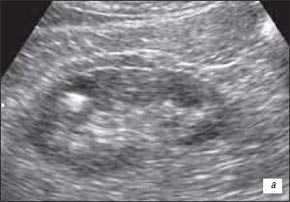

Есть мнение, что дивертикулы чашек или лоханки, пиелогенные кисты при ультразвуковом исследовании практически не выявляются [32], однако, по нашему опыту, это касается только мелких дивертикулов чашечек менее 0,5 см в диаметре (рис. 1) и не относится к дивертикулу чашечки почки больших размеров (рис. 2).

а) Крупная округлая эхонегативная полость, расположенная рядом с лоханкой.

б) Дополнительная полость, сдавливающая лоханку и дугообразно раздвигающая чашечки и лоханку.